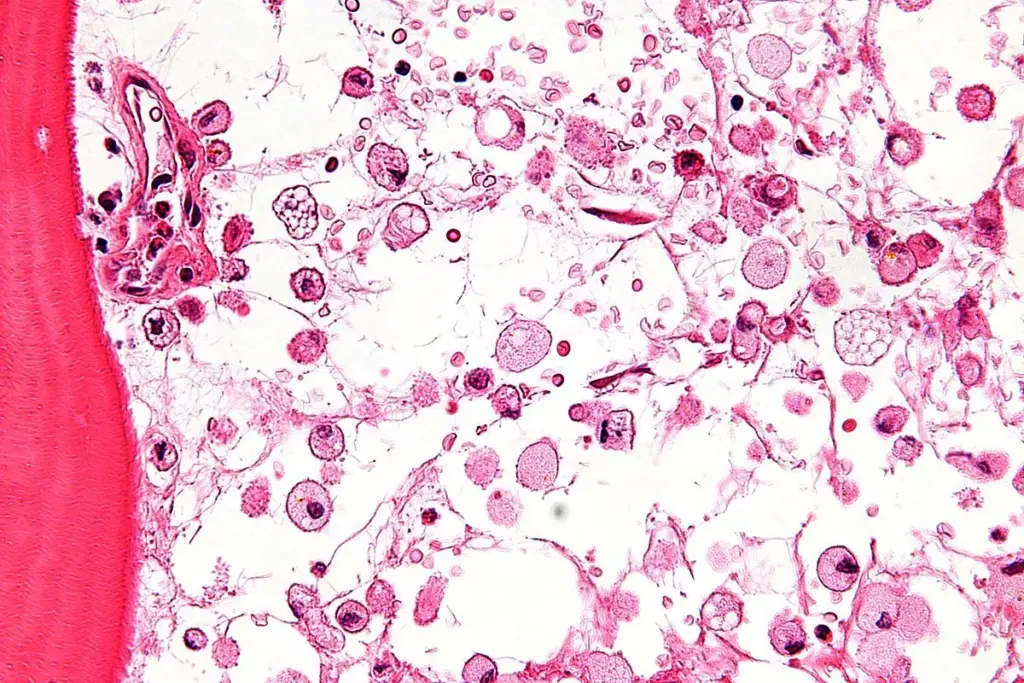

Infiltrative disorders happen when abnormal cells, like cancer, fill the bone marrow. Examples are multiple myeloma and leukemia. They mess up the bone marrow’s job.

Multiple myeloma is a cancer that affects the plasma cells in the bone marrow. It leads to health problems like anemia, bone pain, and infections. shows the struggles of those with this disease.

Multiple myeloma is when cancerous plasma cells build up in the bone marrow. These cells take over, causing symptoms and health issues. The exact cause is unknown, but some risk factors are known.

These cancerous cells produce harmful proteins. These proteins can damage kidneys and other organs. They also block the bone marrow from making healthy blood cells.

Impact on Bone Marrow Function

Cancerous plasma cells harm the bone marrow’s function. It can’t make healthy blood cells, leading to anemia and infections. The proteins from myeloma cells can also damage kidneys and cause other problems.

Bone Marrow Biopsy Experience

A bone marrow biopsy is a more detailed test. It takes a bone marrow sample for study. Done under local anesthesia, it’s usually safe but might hurt a bit.